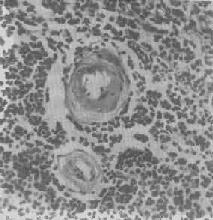

2.血管壁玻璃样变:这种改变常见于高血压病时的肾、脑、脾及视网膜的细动脉。此时,可能是由于细动脉的持续性痉挛,使内膜通透性增高,血浆蛋白得以渗入内膜,在内皮细胞下凝固成无结构的均匀红染物质。此外,内膜下的基底膜样物质增多。这些改变使细动脉的管壁增厚、变硬,管腔变狭,甚至闭塞(图1-20),此即细动脉硬化症(arteri-olosclerosis),可引起肾及脑的缺血。

图1-20 脾中央动脉玻璃样变

>中央动脉管壁明显增厚,呈玻璃样均质状,管腔变窄 ×400